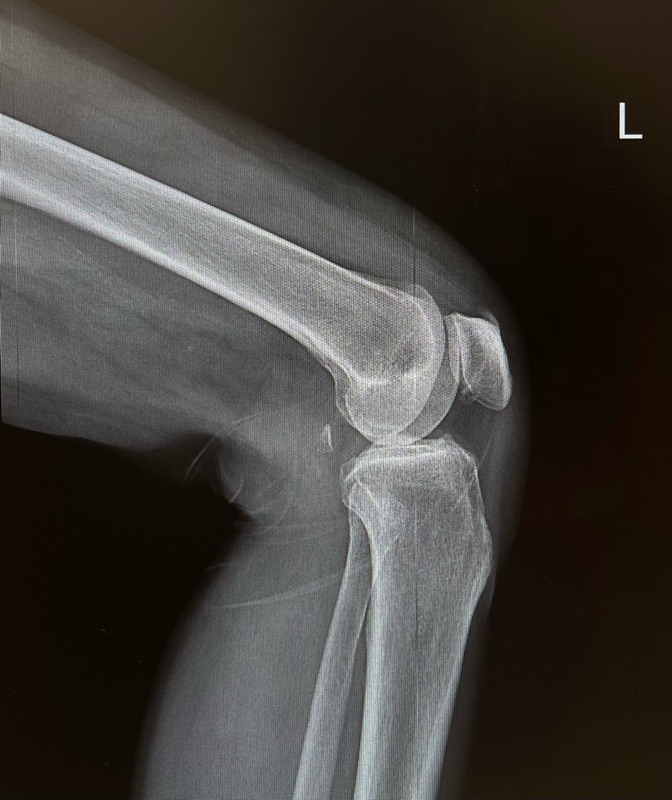

หลังตรวจพบว่าเข่าเสื่อมระดับปานกลาง หมออธิบายว่า อาหารเสริมไม่สามารถแก้ผิวข้อที่สึกแล้วได้ แต่เมื่อเริ่ม